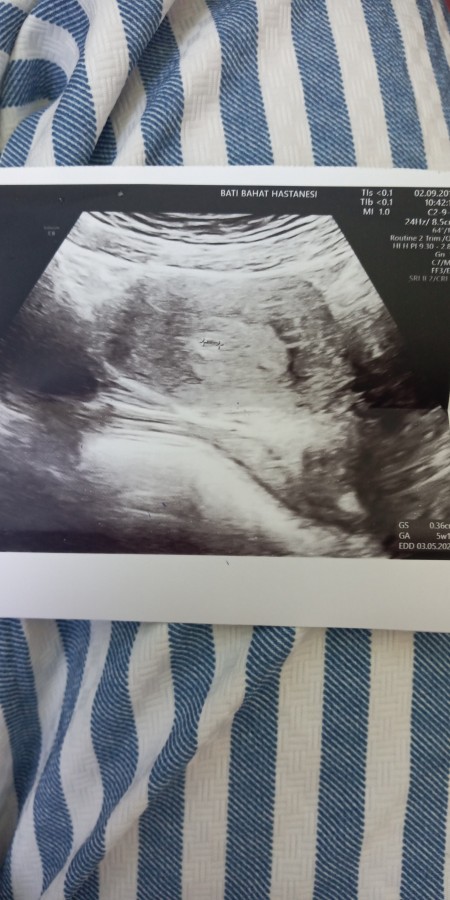

9 Haftalik 2 Aylik Gebelik Bebegin Kalp Atislari Goruluyor Crl Bas Popo Mesafesi 23 Milimetre Youtube